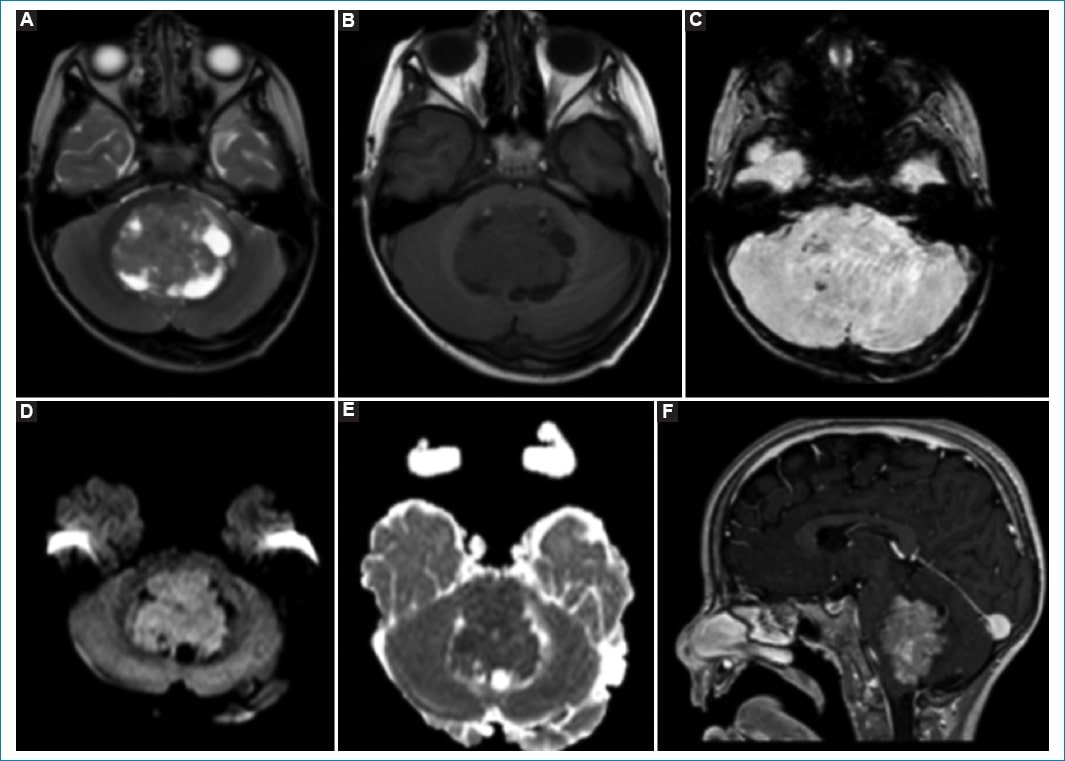

Presentamos el caso de un paciente de 9 años con diagnóstico de meduloblastoma de fosa posterior con metástasis intracraneales al diagnóstico (tercer ventrículo), el cual fue tratado con exéresis quirúrgica subtotal (2017), radioterapia cráneo-espinal (con boost en la fosa posterior) y quimioterapia (finalización en 2018) (Fig. 1).

Figura 1. Formación expansiva predominantemente sólida con áreas quísticas/necróticas en IV ventrículo dilatado, con efecto de masa sobre el parénquima cerebeloso periventricular, desplazamiento y compresión ventral del tronco encefálico, colapsando las cisternas peritroncales. Presenta señal iso-hipointensa ponderada en T1 (A) y T2 (B), con restricción en secuencia DWI (D y E) e imágenes puntiformes hipointensas en SWI (C), pudiendo corresponder a calcificaciones. Secuencia ponderada en T1 poscontraste (F) con refuerzo heterogéneo.